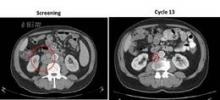

Courtesy Dr. Morschhauser

From baseline screening (image left), treatment with ONO-4059 40 mg resulted in 64% tumor shrinkage at cycle 3 and 89% shrinkage at cycle 13 (image right) in a 69-year-old man with 17p deletion who relapsed on prior therapy with chlorambucil.